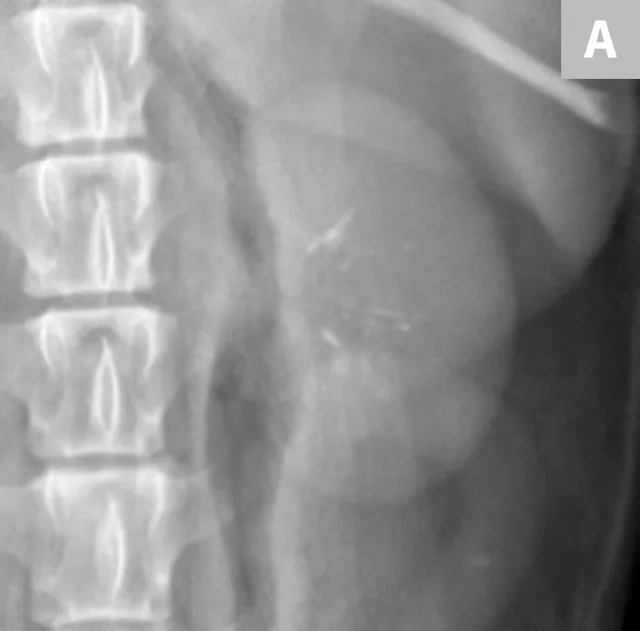

FIGURE 6A

Mild to moderate right hydronephrosis and proximal ureteral dilation in a Dalmatian.